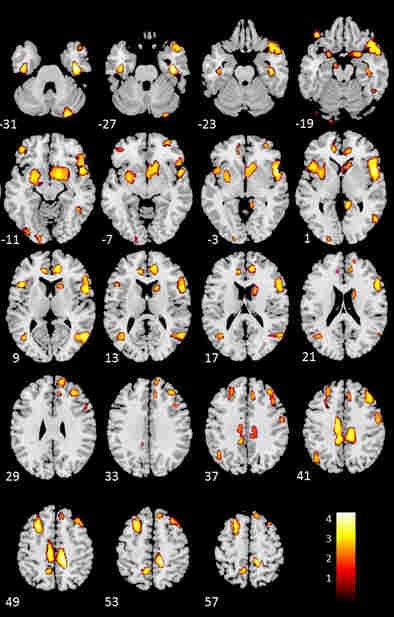

MRI exams correlated with the cardiac findings in the study, demonstrating a relative loss of cerebral gray matter in various cortical and subcortical regions of the brain in patients with heart failure.

Compared with healthy controls, the brain regions of participants with heart failure showed the greatest loss of gray matter in the left cingulate, the right inferior frontal gyrus, the left middle and superior frontal gyri, the right middle temporal lobe, the right and left anterior cingulate, the right middle frontal gyrus, the inferior and precentral frontal gyri, the right caudate, and the occipital-parietal regions involving the left precuneus, the authors reported.

"The relative loss of gray matter among participants with [ischemic heart disease] compared with healthy controls was much less extensive, but affected overlapping regions," including the left medial frontal cortex, the left cingulate and precuneus, the left and right parahippocampal gyri, and the right and left middle temporal gyri.

"Contrary to expectations, our results showed no evidence of cognitive deficits in people with [heart failure compared with ischemic heart disease]," the authors wrote. "However, we found a relative loss of regional [gray matter] among participants with [heart failure] compared with [ischemic heart disease] that was less extensive but had a similar topographic distribution compared to healthy controls, suggesting that the changes may be relatively specific to heart failure."

The structural nature of MRI was useful in demonstrating that people with heart failure display more widespread and extensive brain changes than adults with ischemic heart disease, the authors added.